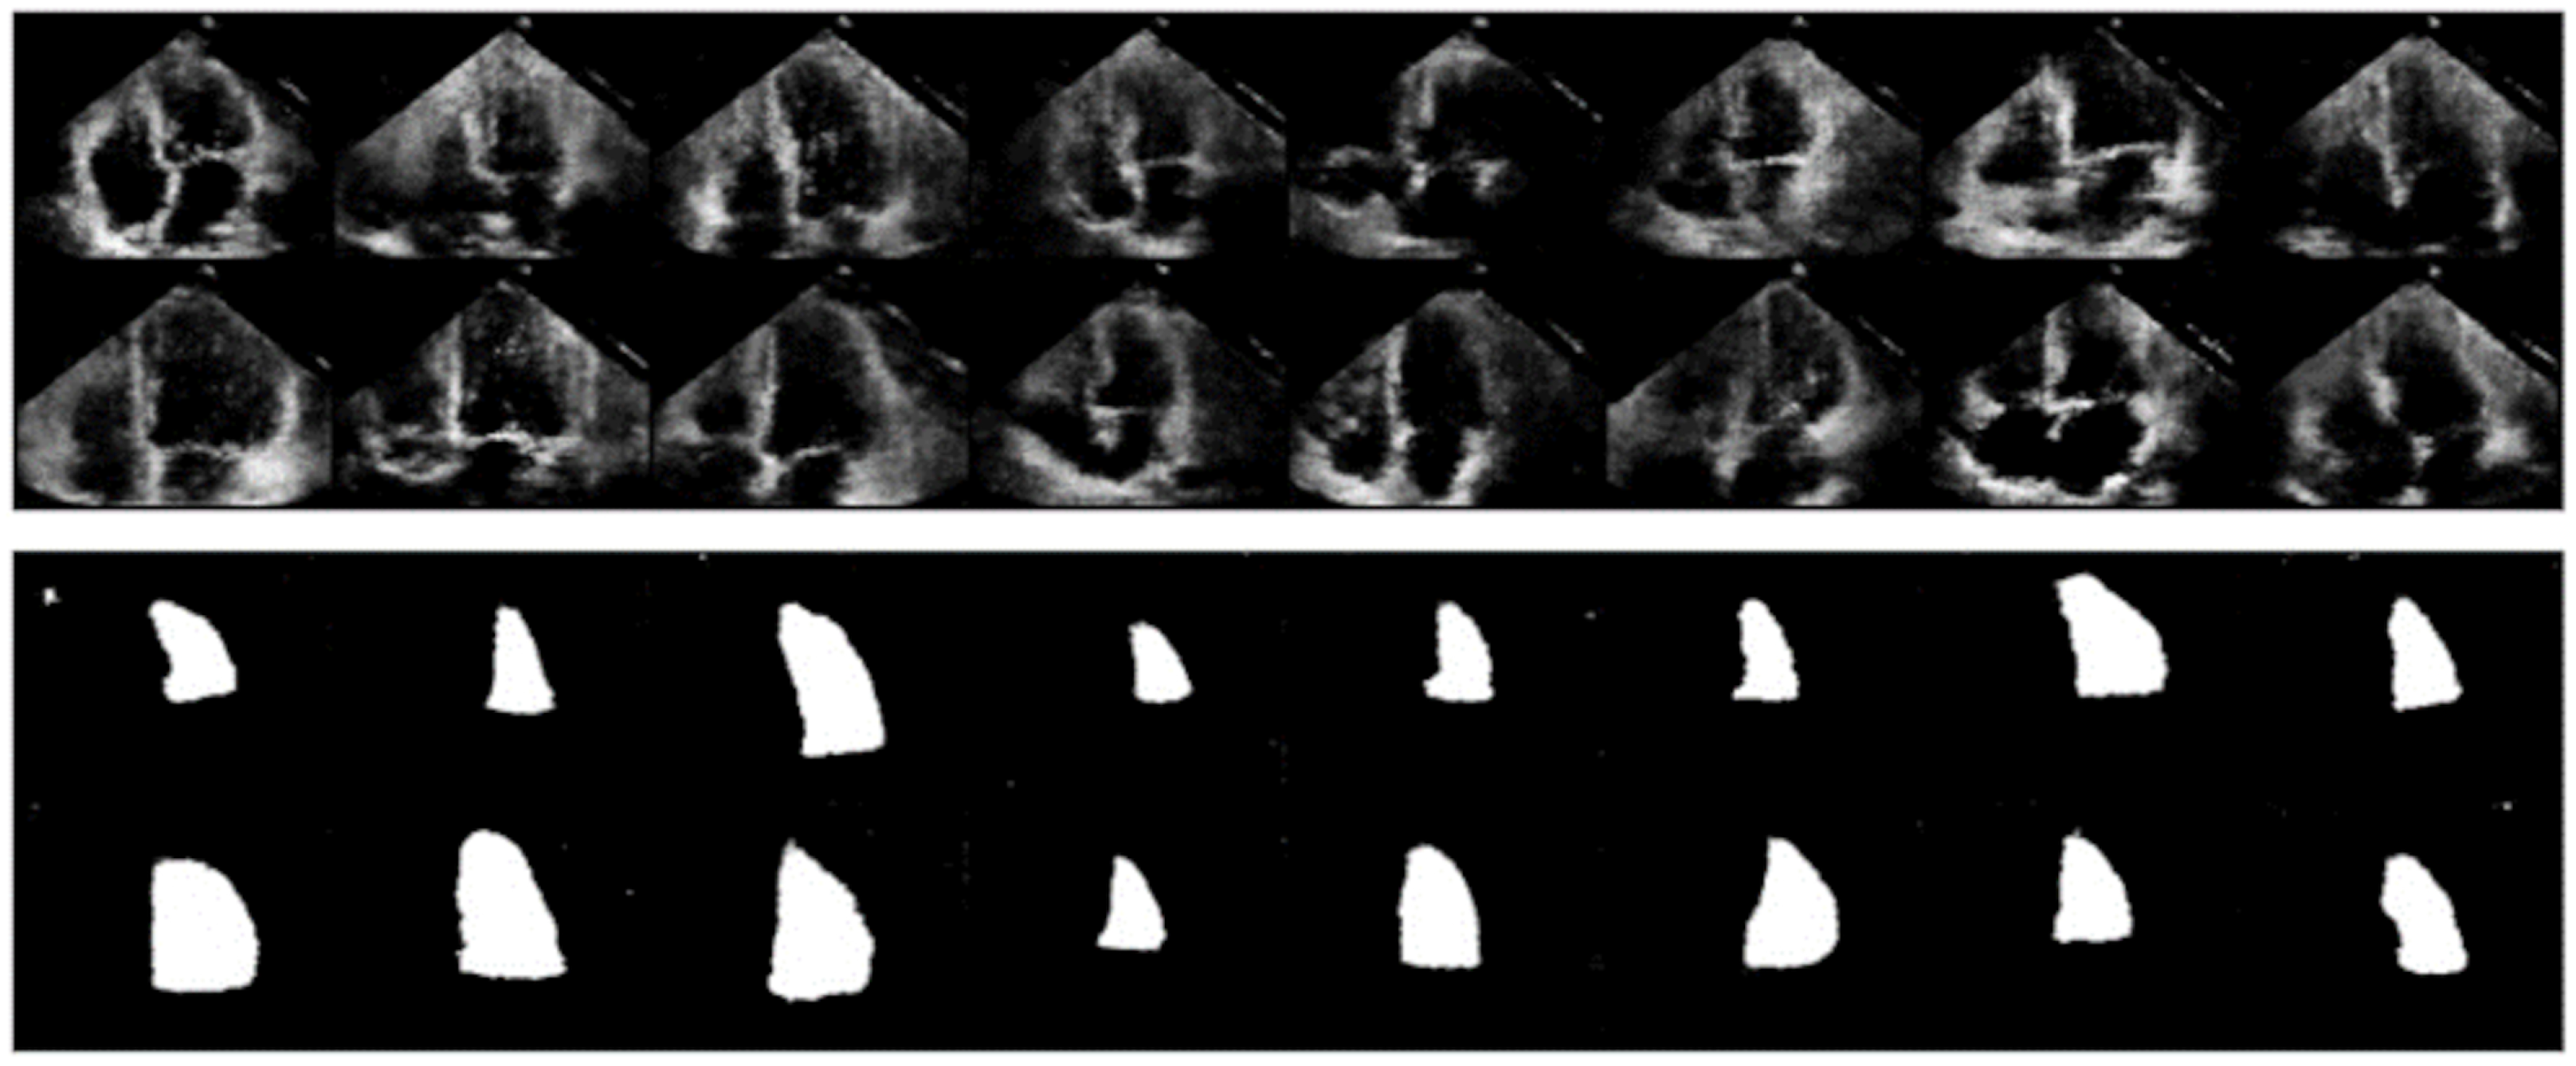

5.1. GAN Architecture

4.1. Data Augmentation with GAN